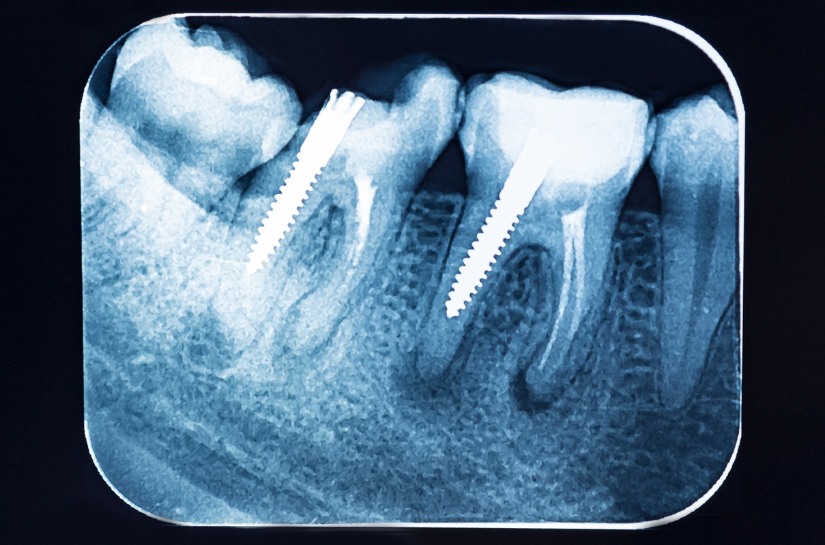

Radiographs or dental x-rays are indispensable tools in any dental treatment plan. Your family dentist’s expertise in examining your teeth visually may not always suffice to unveil underlying issues within your mouth and jaw. Through meticulous scanning, your dentist gains a precise visualization of your teeth and jawbone structure.

To observe your oral cavity accurately, it is imperative to obtain precise imaging from the enamel to the root of your teeth. Dental x-rays offer a comprehensive view of any developing cavities or non-erupted teeth, enabling your dentist to monitor your dental health effectively and devise appropriate treatment measures.

Adults with Restored Teeth: Individuals who have undergone procedures such as crowns, implants, fillings, and bridges should have dental x-rays every 12 to 18 months. This frequency allows for the monitoring of underlying decay and cavity formation. Healthy adults without restoration work can extend their intervals to every 2 to 3 years.